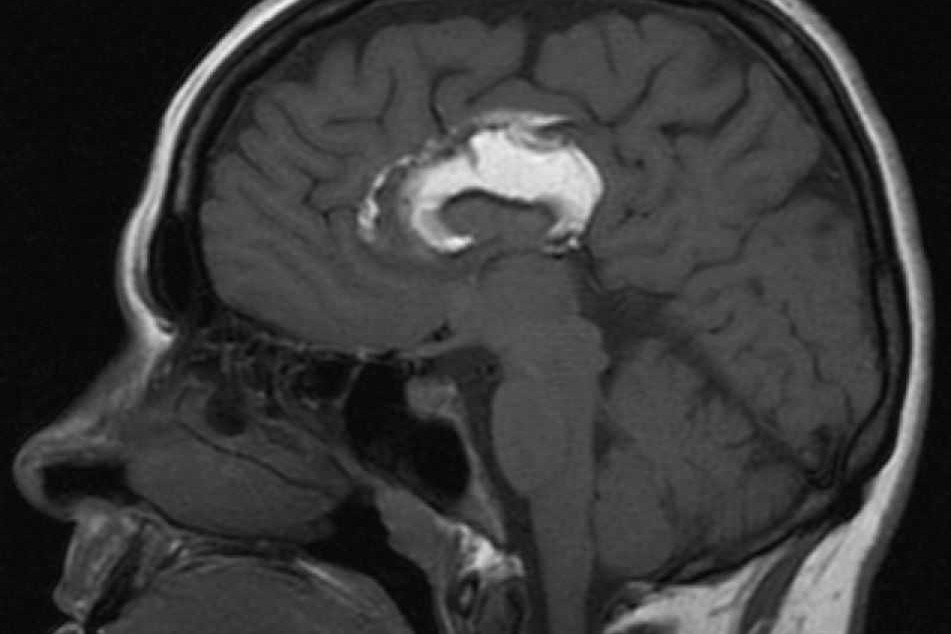

Нейробиологи Томского государственного университета (ТГУ) при поддержке РНФ изучают врожденные аномалии головного мозга детей в пре- и постнатальном периоде. В ходе исследования такой патологии, как агенезия мозолистого тела – отсутствие либо недоразвитие данного отдела головного мозга, было установлено, что его функции могут брать на себя другие мозговые структуры. Благодаря этому когнитивные способности человека в большинстве случаев сохраняются. Новые данные могут кардинально изменить клиническую практику и привести к уменьшению случаев неоправданных прерываний беременности.

Для проведения исследований головного мозга ученые использовали технологию картирования миелина – вещества, из которого состоит оболочка нервных волокон. Уникальный неинвазивный метод разработан нейробиологами ТГУ. Созданные ими протоколы МРТ и специальные алгоритмы обработки изображений позволяют оценивать количество миелина, что является важным показателем при оценке развития головного мозга ребенка или плода. В рамках проекта РНФ ученые ТГУ вместе со специалистами Международного томографического центра СО РАН (Новосибирск) изучают самые ранние стадии формирования миелина в процессе внутриутробного развития плода.

“Мозолистое тело (МТ), отвечающее за связь между полушариями головного мозга, было выбрано в качестве объекта исследования не случайно, – объясняет ведущий научный сотрудник, заведующая отделением медицинской диагностики Международного томографического центра (МТЦ) СО РАН, доктор медицинских наук Александра Коростышевская. – Аномалии развития мозолистого тела встречаются нередко. Среди всех аномалий развития головного мозга нарушение строения его срединных структур занимает 47%, из них 40% связаны с недоразвитием (агенезией) мозолистого тела. Жизненный прогноз для таких детей пока однозначно не определен. Поэтому врачи и родители стоят перед крайне сложным выбором: оставить беременность с риском рождения умственно неполноценного ребенка либо прервать ее”.

Увидеть особенности аномалии с помощью пренатального УЗИ возможно далеко не всегда. Почти в половине случаев при подозрении на агенезию мозолистого тела необходима МРТ головного мозга плода. МРТ плода – обследование технически сложное, поскольку плод, плавающий в амниотической жидкости, почти постоянно пребывает в движении. Специалисты Международного томографического центра СО РАН одними из первых в РФ внедрили эту диагностическю технологию в 2008 году и более 13 лет совершенствуют ее.

“За время реализации нашего проекта была набрана репрезентативная выборка плодов с агенезией мозолистого тела, – рассказывает руководитель проекта, научный руководитель лаборатории нейробиологии НИИ ББ ТГУ, профессор ТГУ и Вашингтонского университета Василий Ярных. – При их сравнении с плодами без отклонений от нормы мы увидели картину, которая оказалась совершенно неожиданной: развитие миелина в центральных структурах головного мозга у плодов с отсутствием мозолистого тела происходит значительно быстрее, чем у нормальных плодов. Другими словами, задержка или отсутствие развития одного отдела головного мозга компенсируется развитием других его структур, и они берут на себя функцию связующего звена между полушариями”.

“Мы изучаем плод на той стадии развития, когда миелин только начинает формироваться, – говорит Василий Ярных. – На основании изучения карт миелина мы увидели, что ускоренная миелинизация при агенезии мозолистого тела происходит в продолговатом мозге и распространяется на мозжечок. Это позволяет предположить, что стволовые структуры мозга могут брать на себя функцию связи между полушариями. Ранее считалось, что компенсаторные связи при отсутствии мозолистого тела обеспечивают другие зоны мозга, в которых миелин формируется уже после рождения. Мы получили фундаментально новые данные, которые меняют привычное представление о том, как происходит взаимодействие между различными отделами головного мозга”.